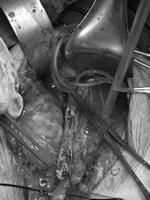

血管外科副主任崔文军亲自与邹大爷家属做术前沟通,通过画图详细说明了此次的手术方式及可能存在的风险,最终取得邹大爷家属的理解和赞同。手术由王兵教授亲自操刀,通过腹膜后入路,在不干扰肠管的情况下,成功露出左侧的髂动脉及股总动脉,但术中血管的情况还是出乎大家的意料,整个髂动脉都如骨头般坚硬,没有丝毫的弹性,大大增加了手术难度。最终,王兵教授凭借精湛的技术,在患者股总及髂外动脉行多个小切口(图2),不仅取出了陈旧血栓(图3),也完整剥脱了髂动脉增生的内膜及斑块(图3)。分段小切口的目的,一方面可完整剥脱斑块,最重要的是可以有效降低血管的再狭窄率,起到良好的远期通畅效果。术后当天邹大爷就感觉到自己的左脚没有那么凉、那么疼了。第二天,王兵教授到病房楼查看邹大爷术后恢复情况,邹大爷紧紧握着王兵教授的手说:“谢谢王教授,让我终于睡了个安稳觉!”术后,在施敏护士长带领的护理团队精心护理下,目前邹大爷康复良好,未出现任何并发症。

图2

图3